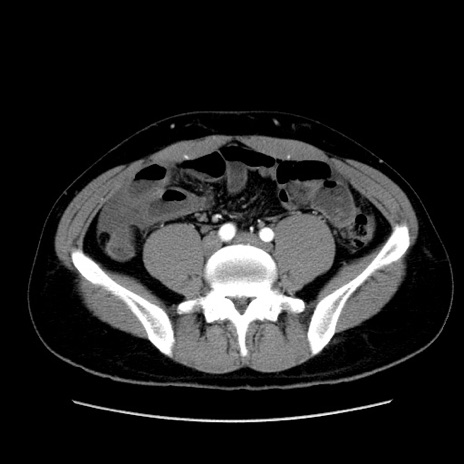

症例36(横断像)

【症例】20歳代 男性

【主訴】心窩部痛

【現病歴】今朝より上腹部痛あり。一旦軽快していたが再度出現したため救急要請。昨日夕に白身の魚を含む刺身を食べた。

【身体所見】BP 136/89mmHg、HR 74/min、BT 37.0℃、腹部:膨満、軟、心窩部に圧痛あり。反跳痛なし、筋性防御なし、腸雑音やや亢進あり。

【データ】WBC 17700、CRP 0.48